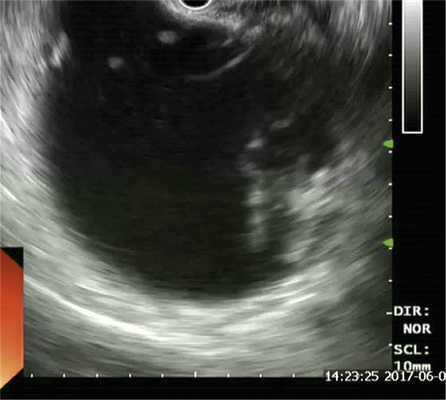

Для определения возможности эндоскопического дренирования гигантской псевдокисты пациенту была выполнена эндоскопическая ультрасонография, по данным которой в проекции головки-хвоста ПЖ определись два крупных жидкостных коллектора с ровными четкими контурами размерами 170×130 и 120×180 мм. Оба жидкостных скопления имели четкие границы, были правильной овальной и округлой формы с гиперэхогенной капсулой толщиной до 3 мм и содержали значительное количество гиперэхогенного содержимого с неровными контурами — секвестры. ПЖ просматривалась фрагментарно, контуры ее четкие и неровные, структура диффузно неоднородная, сниженной эхогенности, панкреатический проток в доступных участках не визуализировался (рис. 3).

Рис. 3. Эндоскопическая ультрасонограмма (псевдокиста с секвестром).